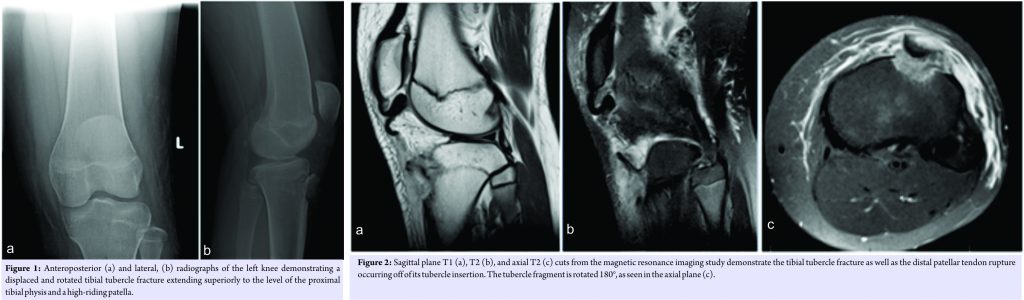

The patient is a 13-year-old girl with no prior medical history who fell while skateboarding onto a hyper flexed left knee on the day of presentation. She experienced an immediate onset of knee pain with subsequent swelling and was unable to ambulate due to pain and weakness in her left leg. A review of systems was negative for sensory abnormalities or pain in other anatomical locations. On physical examination, the skin over the left knee was intact with no abrasions or open wounds. There was diffuse soft tissue swelling around the knee as well as a moderate knee joint effusion. She had exquisite tenderness to palpation directly over the tibial tubercle and patellar tendon, with an asymmetrically high-riding patella on palpation compared to the contralateral extremity. Although she was unable to straight leg raise against gravity, she was able to perform the maneuver with gravity eliminated, with moderate pain. Distally, she demonstrated full motor strength with ankle and great toe dorsi-and plantar flexion. Her sensation was grossly intact to light touch in all distributions distally. After examination, she underwent plain film imaging (Fig. 1), which demonstrated a displaced tibial tubercle fracture extending to the level of the proximal tibial physis (Ogden Type IIB) with concomitant patella alta. Given the latter finding, concern was raised for patellar tendon injury, and magnetic resonance imaging was obtained which demonstrated a patellar tendon rupture at the tubercle insertion site (Fig. 2).